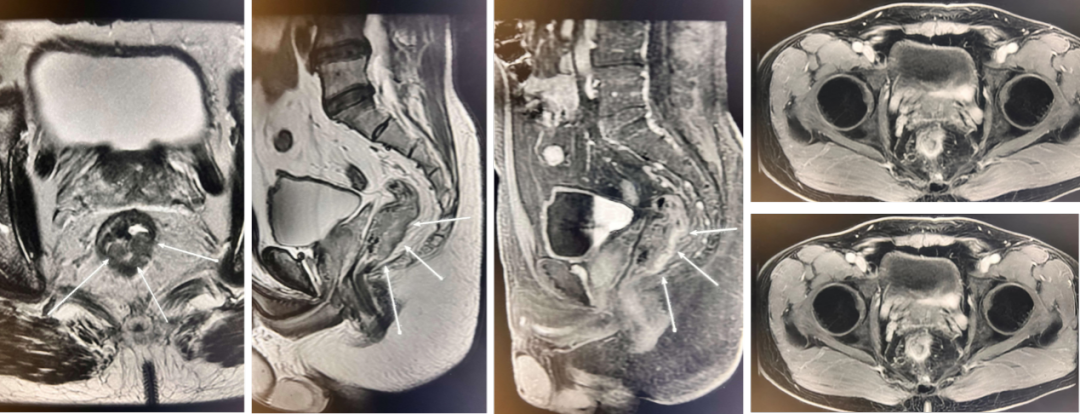

在全球,结直肠癌是发病率位居第三位、病死率位居第二位的肿瘤。肠镜筛查的普及以及手术方式的提升显著降低了结直肠癌的死亡率,但仍有一部分患者在初诊时已发展为晚期,失去手术根治的机会,且预后较差,5年生存率仅12%。许多转移性结直肠癌(mCRC)患者在经历一线治疗后,面临无药可用的困境。近年来,随着靶免联合治疗在系统治疗中逐渐前移,各种靶向治疗药物在mCRC的诊疗中也越发举足轻重。本文分享2例晚期结肠癌患者的诊疗经过,呈现瑞戈非尼在二线治疗为患者带来长生存的治疗价值及其良好的后线应用前景,以期为临床医生提供诊疗借鉴。 病例提供:海军军医大学附属长征医院 王湛 王湛 病例基本情况 一般信息:女 ,58岁。2020年10月,患者无明显诱因出现腹胀,无伴随症状,未予重视。后腹胀进行性加重,2020年11月中旬下腹部隐痛,与进食及体位变化无关,无肩背部放射痛。 辅助检查: 腹部超声:腹腔积液。 腹水脱落细胞病理:腺癌。 腹部增强CT:结肠肝曲癌;腹盆腔积液,腹盆腔腹膜多发转移。 结肠镜(2020-12-4):升结肠近肝曲见隆起型新生物,范围约4cm,新生物表面分叶状,质脆,触之易出血。肠腔狭窄,内镜尚可通过。 2020-12-8病理:横结肠,中分化腺癌,含部分粘液腺癌。 一线治疗2020-12-03至2021-02-24 CAPEOX+贝伐珠单抗 治疗4周期 病情进展,腹胀、腹痛加重,腹水增加。 2021-3-31 PET-CT:腹腔内及腹膜、脾脏、纵隔及右侧心膈角区、左侧锁骨区多发代谢增高灶,结合病史,考虑转移;双肺转移;腹腔及盆腔积液;结肠显示欠清,请结合肠镜检查;双侧胸腔少量积液,左肺下叶部分不张;双肺少许慢性炎症;右肝血管瘤;左肾结石。;子宫术后,痔疮可能;脊柱退变,腰3不稳,腰3/4、4/5、腰5/骶1椎间盘突出。 PFS:3个月 2021-4-6,完善基因检测(腹水标本):KRAS/APC/TERT/TP53/ target=_blank class=infotextkey>P53 突变,TMB 7.98/Mb,MSS 二线治疗,2021-04-02至2021-12 2021-3-31 2021-6-2 2021-8-6肠镜:结肠镜顺利插至回盲部,回盲瓣呈唇状。结直肠粘膜呈桔红色,光滑湿润,有光泽。血管纹理呈树枝状,清晰可见。 PFS:8月 三线治疗,2021-12-13至2022-01-23 三氧化二砷 2021-6-2 2021-11-22 2021-11-22 2022-2-8 PFS:2月 四线治疗,2022-02-10 化疗+免疫+瑞戈非尼+三氧化二砷 2022-2-10开始使用小剂量化疗(雷替曲塞+奥沙利铂+伊立替康)+免疫(信迪利单抗)+瑞戈非尼+三氧化二砷治疗。 疗效评估(2022-9-20):患者病情再次取得缓解。 2022-9-22至今采用维持治疗,降低治疗强度:雷替曲塞 +信迪利单抗+瑞戈非尼+三氧化二砷 2022-9-20 2023-2-8 PFS:13个月+ 该患者为中年女性,诊断为晚期多发转移性结肠癌,基因检测提示KRAS突变,BRAF、NRAS野生型,微卫星稳定,无法进行根治性切除。一线治疗加予CAPEOX联合贝伐珠单抗,治疗4周期后出现病情进展,腹胀、腹痛加重,腹腔积液增加,二线采用瑞戈非尼联合免疫和化疗,患者耐受良好,1周期后腹胀明显缓解,全身状态、PET-CT、肠镜结果较之前明显改善,继续原方案治疗,PFS长达8月。二线治疗进展后完善基因检测,发现TP53 突变,经与患者充分沟通,三线治疗采用三氧化二砷,疗效不佳。四线治疗在三氧化二砷基础上加用瑞戈非尼+免疫+化疗,患者病情再次取得缓解,PFS 超过13个月。近年来,随着精准医学及靶向、免疫治疗的发展,mCRC的管理与治疗策略的制定也变得复杂,合理选择治疗手段、优化全程管理至关重要。本例患者经历了一线化疗联合免疫治疗后疾病出现快速进展,我们个体化地在二线治疗中应用瑞戈非尼联合方案,患者疾病得到控制,PFS 8个月。在四线治疗方案中,再次挑战瑞戈非尼,依然获得较好的疾病控制效果,目前PFS已超过13个月。基于CORRECT和CONCUR研究,瑞戈非尼用于mCRC三线治疗已积累大量临床数据,目前已成为mCRC三线标准治疗方案。此外,REGONIVO、REGOTORI以及RIN方案证实了瑞戈非尼联合免疫治疗MSS型肠癌取得更长的总生存期。一线治疗后疾病进展,能否将瑞戈非尼使用前移,在二线治疗中加用以进一步延长患者生存,以及前线已经暴露过瑞戈非尼,后线再次使用瑞戈非尼是否可行,仍待在临床研究中进一步证实。 02 病例分享二 病例提供:海军军医大学第一附属医院 王薇 王薇 病例基本情况 一般信息:男性,41岁。2020年10月8日,无明显诱因下出现便血,为鲜红色,伴肛门坠胀不适,无排便习惯改变,无腹胀,无消瘦。1997年因“胃溃疡”行胃部幽门切除术;2019年行混合痔手术。 辅助检查: CEA 3.4ng/ml,CA199 3.52u/ml。 当地医院肠镜(2020-11-20):(距肛缘8-10cm)可见粘膜不规则隆起,表面溃烂,易出血。 肠镜活检病理:(直肠)中分化腺癌。 盆腔MRI增强(2020-11-26):直肠中段癌,考虑mrT3N1Mx,MRF-,EMVI-。 肝脏MRI增强(2020-11-27):未见明显异常。 治疗经过 首次手术治疗2020-12-09 腹腔镜辅助直肠癌拖出式适形切除术+末端回肠造口术 术中探查:直肠下段肿物,质硬,未浸润浆膜层,周围系膜未见肿大淋巴结。肿瘤大小约4*4*2cm,占肠腔1/2周,系膜完整。 术后病理: 直肠溃疡型肿瘤大小4.5x3.5x1.5cm;中至低分化腺癌,部分为粘膜腺癌;浸润至外膜层; 癌结节( 3枚+)、脉管癌栓(+)、神经侵犯(+)、肿瘤出芽(+,PDC1级);上下切缘(-)、环周切缘(-)、吻合圈(-);周围淋巴结(2/6),直肠外膜淋巴结(2/4),最高群淋巴结(0/4); 基因分型:KRAS Exon-2 G12D突变,NRAS、BRAF、PIK3野生型;免疫组化:MSH2(+),MSH6(+),MLH1 (+),PMS2(+),pMMR;Ki-67 80%。 术后分期:pT3N2aMx IIIB期 术后辅助治疗(XELOX方案) XELOX方案化疗3周期; 拟行盆腔放疗50gy/25次,2021-03-25起放疗6次 术后复查 肝脏MRI增强(2021-03-27):肝脏多发结节,较前为新发,考虑肝内多发转移瘤 一线治疗,2021-04-22至2021-06-24 mXELIRI+贝伐珠单抗 治疗4周期 患者治疗后出现恶心呕吐,胃纳明显减退,Ⅱ°粒细胞下降,腹泻,脱发,轻度手足皮肤反应,手足冰凉,心悸。患者无法耐受继续治疗 维持治疗,2021-7-15至2021-8-26,卡培他滨+贝伐珠单抗,共计治疗3周期 肝脏MRI增强(2021-5-31、2021-8-24):肝右后叶上段7mm小结节灶,转移不除外,腹膜后稍大淋巴结较前相仿,随访。 2021-3-27与2021-5-31的肝脏MRI增强对比图 2021-8-24 肝脏MRI增强 盆腔MRI增强(2021-8-25):术区及骶前软组织肿胀,左侧条索影,结合CT考虑术区置管术后改变,较2021-06-01片大致相仿。 疗效评估:PR 后患者诉心悸、乏力、胃纳不佳;血压正常;心肌酶正常;心脏彩超LVEF 64%;EKG: 窦性心率,T波低平;尿蛋白(-)。患者对化疗非常抗拒。 二线治疗,2021-09-17至2021-12-15 盆腔MRI增强(2022-9-13):术区及骶前软组织肿胀,左侧条索影,结合CT考虑术区置管术后改变,较前片大致相仿。 胸部CT(2022-9-13): 右肺下小结节,随访。 疗效评估:PR。 2022-12-20肝脏MRI增强:平扫+增强未见明显异常。 2022-12-21盆腔MRI增强:直肠癌术后,盆腔区未见明显复发及转移病灶。 病例总结 该患者为中年男性,诊断为局部晚期直肠癌,原发灶术后分期IIIB期,基因检测KRASExon-2G12D突变、微卫星稳定。术后仅3月余在XELOX方案辅助化疗、盆腔放疗期间出现多发肝转移,疾病进展转移灶不可切除,进而接受XELIRI方案联合贝伐珠单抗二线全身治疗。治疗后肝脏多发转移瘤退缩理想,病灶明显缩小减少。但患者治疗副反应不可耐受,改卡培他滨联合贝伐单抗治疗后持续有效,但仍无法耐受副反应。遂予以瑞戈非尼靶向治疗:120mg日剂量口服,服用三周停用一周至今。患者耐受良好,近期复查未发现明显复发转移病灶。目前二线PFS已达23个月,瑞戈非尼二线维持治疗DoR17个月。目前,二线治疗在不同患者亚群的优选方案仍存在争议。而整个系统治疗到了三线阶段,标准治疗主要价值是能够延长患者的疾病控制时间,缩瘤效果和客观缓解率均不理想,并没有满足目前的治疗需求。根据目前的药物机制和临床研究结果,考虑到患者的具体情况:涵盖治疗目标、体质状况、对预估的不良事件的耐受性及是否存在相关危险因素、既往治疗用药情况等方面,我们采用了个体化的瑞戈非尼二线维持治疗方案取得良好疗效,这种治疗策略希望能在规范临床研究中证实。病例分享一